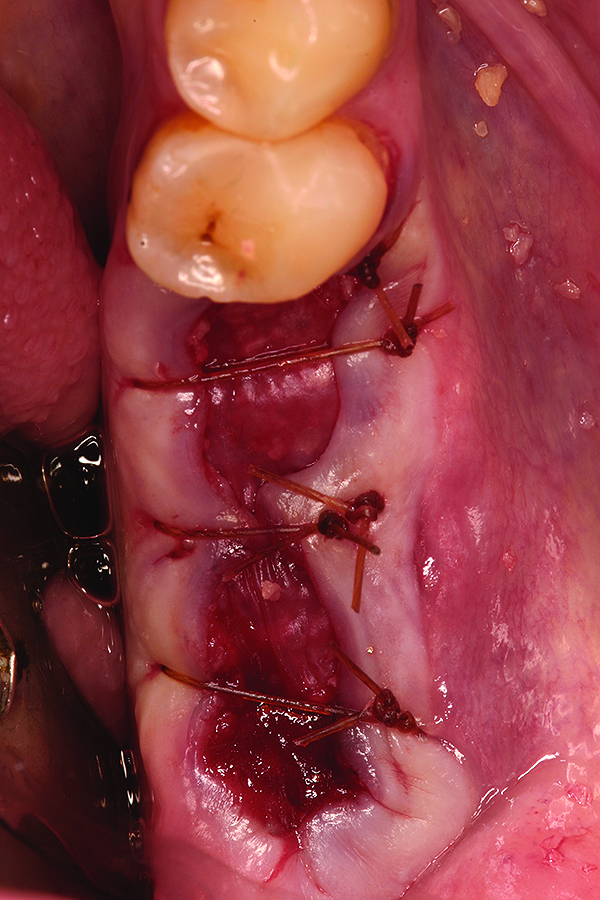

Fig 11. Intentional non-primary closure following the placement of an amnion-chorion barrier over the bone allograft.

Figure 11